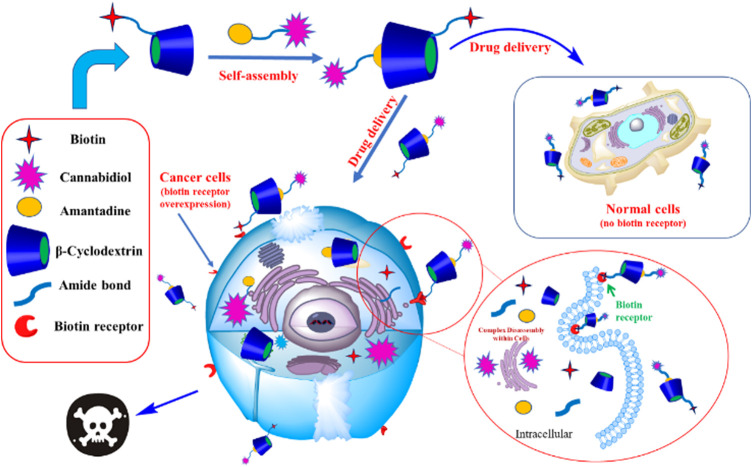

Cannabidiol (CBD) is one specific kind of the cannabinoid in Cannabis sativa L with a wide range of pharmacological activities. However, the poor water solubility and specificity of CBD limits its application in pharmaceutical field. For solving these problems, in this work, we successfully prepared a targeted carrier by grafting biotin (BIO) onto ethylenediamine-β-Cyclodextrin (EN-CD) in a single step to generate a functionalized supramolecule, named BIO-CD. Subsequently, an amantadine-conjugated cannabinoids (AD-CBD) was prepared and self-assembled with the BIO-CD. A series of methods were used to characterize the inclusion behavior and physicochemical properties of AD-CBD and BIO-CD. The results showed that AD-CBD entered the cavity of BIO-CD and formed a 1:1 host-guest inclusion complex. MTT assay and confocal laser scanning microscopy (CLSM) revealed that the targeting effect and anticancer activity of AD-CBD/BIO-CD inclusion complex against three human cancer cell lines were higher than BIO-CD, AD-CBD and free CBD. Moreover, the inclusion complex could release drugs under weakly acidic conditions. These results demonstrated that AD-CBD/BIO-CD inclusion complex possess excellent targeted and anticancer activity, which is hopeful to be applied in clinic as a new therapeutic approach.

The development of molecular biology and cell biology has promoted the emergence of targeted drugs for the treatment of cancer. (ref. Pang et al., 2019; ref. Hajeri et al., 2020). Targeting technology facilitates drug delivery because it deposits the drug in the desired location to achieve the most effective treatment of the disease (ref. Zhang et al., 2018a). An obvious solution to the lack of targeting ability of natural cyclodextrin is to modify the targeting group of cyclodextrin. Biotin (BIO), also known as vitamin H, is a good targeting ligand, as its receptor can be overexpressed in many cancer cells (ref. Singh et al., 2010; ref. Rompicharla et al., 2019; ref. Zhang et al., 2018b) such as lung cancer cells, colon cancer cells, kidney cells, ovarian cancer cells, and breast cancer cells. More excitingly, it is rarely expressed in normal cells (ref. Lv et al., 2017). Furthermore, when the functional groups are exposed outside the cavity of CDs, the anti-tumor activity of most drugs can be enhanced (ref. Jiao et al., 2012; ref. Zhang et al., 2018a). For this reason, amantadine was used to modify CBD (AD-CBD). Adamantane interacts with cyclodextrin to form a stable complex, ultimately exposing the CBD to the outside of the CDs cavity (ref. Rompicharla et al., 2018). The characterization and inclusion behavior of inclusion complex of amantadine conjugated cannabinoid (AD-CBD) and biotin-ethylenediamine-β-cyclodextrin (BIO-CD) in solution and solid state were studied by various methods, while the water solubility and anti-tumor activity of the inclusion complex were tested in our study.

Job plot analysis can confirm the stoichiometric ratio of the inclusion complex. The Job plot of the AD-CBD/BIO-CD was shown in Figures 1, 2. Based on this method, the F value associated with the maximum value of ΔAbs × F was considered the stoichiometric proportion. The peak values of ordinate occurred at 0.5 as shown in Figure 2, which demonstrated that the stoichiometric ratio of the host and guest was 1:1. This was consistent with the results of the previous study that adamantane and ß-cyclodextrin could form a 1:1 inclusion complex.

In Vitro Release Property

In Vitro Cytotoxicity Studies

The prerequisite for drug delivery is biocompatibility. In the cytotoxic test under different incubation times, the BIO-CD exhibited high biocompatibility (Table 3). Besides the established biodegradability of previous study, it also had biocompatibility of practical drug delivery applications. Since CBD enhanced cellular uptake by the biotin receptor mediated cellular uptake, the cytotoxicity of AD-CBD/BIO-CD was enhanced, as shown in the following experiments.

Therefore, the feasibility of targeted drug delivery of using BIO-CD was evaluated in our study. The model drug Rhodamine B was used to demonstrate that the BIO-CD polymer delivered the drug selectively to the biotin receptor overexpressed cancer cells. The two cell lines of HeLa cervical cancer and A549 human lung cancer have different biotin receptor expression levels on the cell membranes, thence, they are used as cell models. From the confocal image, the copolymer loaded with Rhodamine B was combined with HeLa cells selectively. But the fluorescence of the cell surface of A549 was negligible, indicating the biotin receptor targeting ability of BIO-CD (Figure 12).

In the pharmaceutical and biomedical materials industry, the supramolecular drug carrier with targeted function has a very promising research value. A host-guest complex of BIO-CD/AD-CBD based on supramolecular self-assembly, with targeted capability and pH-dependent release was designed and prepared in this study. Among them, inclusion complexes of AD-CBD/BIO-CD exhibits excellent anti-cancer activity, biocompatibility, controlled release ability, and selective delivery ability to the cancer cells, overexpressing biotin receptors. Therefore, this targeted host-guest complex is a promising approach for the treatment of cancer.